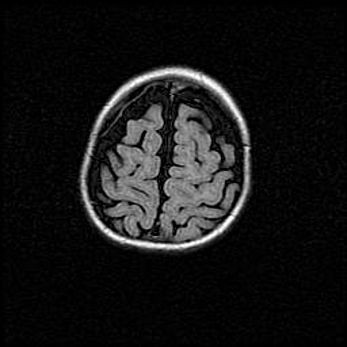

Открытая гидроцефалия.

Возраст: 9 месяцев 12 дней

Вес: 6800 г

Пол: мужской

Окружность головы: 41,5 см

Срок гестации: 28 недель

Гидроцефалия головного мозга у новорожденных имеет характерный признак: опережающий рост окружности головы приводит к визуально хорошо определяемой гидроцефальной форме сильно увеличенного в объёме черепа. Детские неврологи определяют следующие симптомы гидроцефалии у грудничков: выбухающий напряжённый родничок, частое запрокидывание головы, смещение глазных яблок к низу.